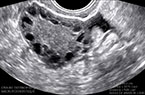

Ovaire dystrophique micropolykystique : caractéristiques échographiques Ovaire dystrophique micropolykystique : caractéristiques échographiques Ovaire dystrophique micropolykystique : caractéristiques échographiques